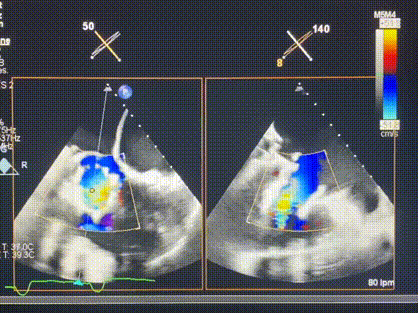

術(shù)中輸送器在超聲引導(dǎo)下調(diào)整位置

手術(shù)在全麻狀態(tài)下進(jìn)行。術(shù)者采用經(jīng)右側(cè)頸靜脈入路的方式將輸送器送入患者心臟內(nèi),在TEE及DSA引導(dǎo)下調(diào)整輸送器頭端角度,使得輸送器與三尖瓣瓣環(huán)平面垂直。在輸送器進(jìn)入右心室后釋放室間隔錨定裝置,而后釋放瓣葉夾持件(2個(gè)耳片結(jié)構(gòu))成垂直狀態(tài)。在TEE及DSA確定夾持件固定至三尖瓣葉根部且位于右室側(cè)后釋放人工瓣心房側(cè)盤片。隨后調(diào)整瓣膜同軸性以及室間隔錨定件位置(貼合室間隔),前推藏針管并固定,進(jìn)而釋放室間隔錨定裝置,并再次確認(rèn)瓣膜位置、穩(wěn)定性及同軸性,合攏輸送鞘后撤出輸送器,完成LuX-Valve Plus人工三尖瓣瓣膜的植入,僅殘余微量瓣周漏。且經(jīng)手術(shù)中心電生理團(tuán)隊(duì)評(píng)估,病人的起搏器和ICD功能沒(méi)有受到影響。

術(shù)后超聲顯示僅殘余微量瓣周漏